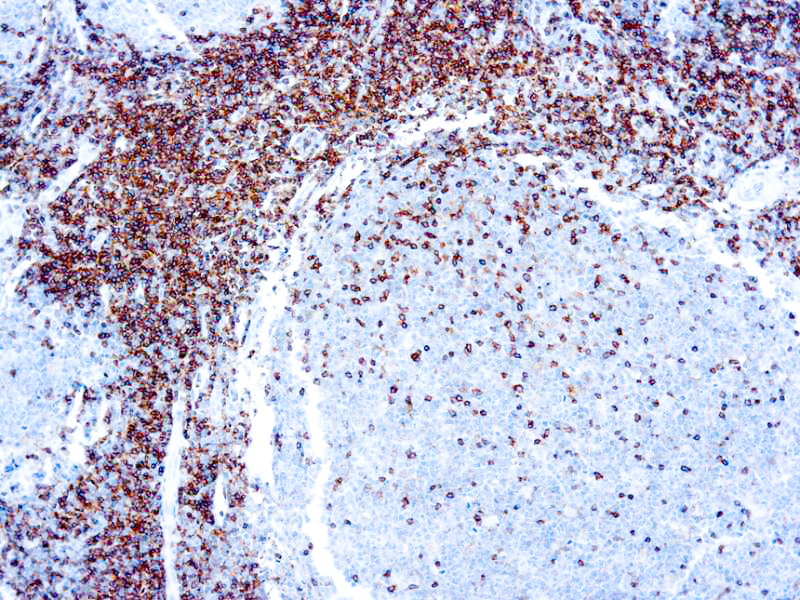

Leukocyte Common Antigen (LCA)/CD45

CD45R, also designated CD45 and PTPRC, has been identified as a transmembrane glycoprotein, broadly expressed among hematopoietic cells. Multiple isoforms of CD45R are distributed throughout the immune system according to cell type. These isoforms arise because of alternative splicing of exons 4, 5, and 6. The corresponding protein domains are characterized by the binding of monoclonal antibodies specific for CD45RA (exon 4), CD45RB (exon 5), CD45RC (exon 6) and CD45RO (exons 4 to 6 spliced out). The variation in these isoforms is localized to the extracellular domain of CD45R, while the intracellular domain is conserved. CD45R functions as a phosphor-tyrosine phosphatase. Antibody to CD45 is useful in differential diagnosis of lymphoid tumors from non-hematopoietic undifferentiated neoplasms.

| Positive Control Tissue | Tonsil |